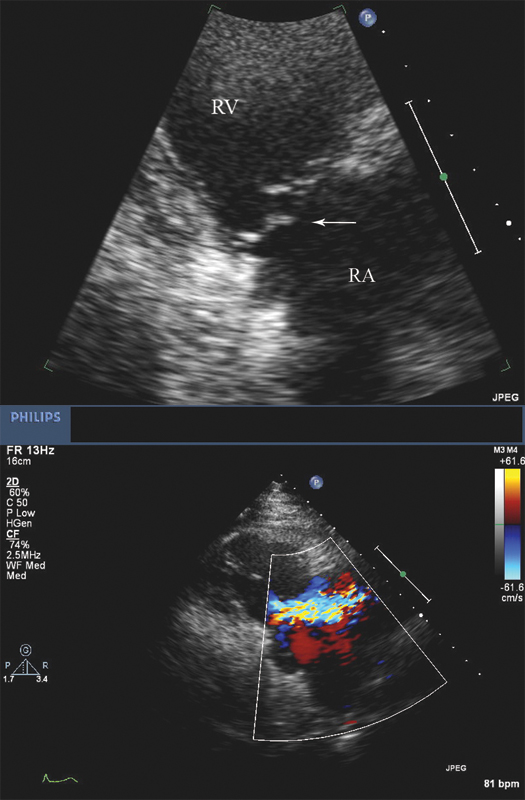

فحوصات تشخيصية لبعض امراض القلب والشرايين التاجية